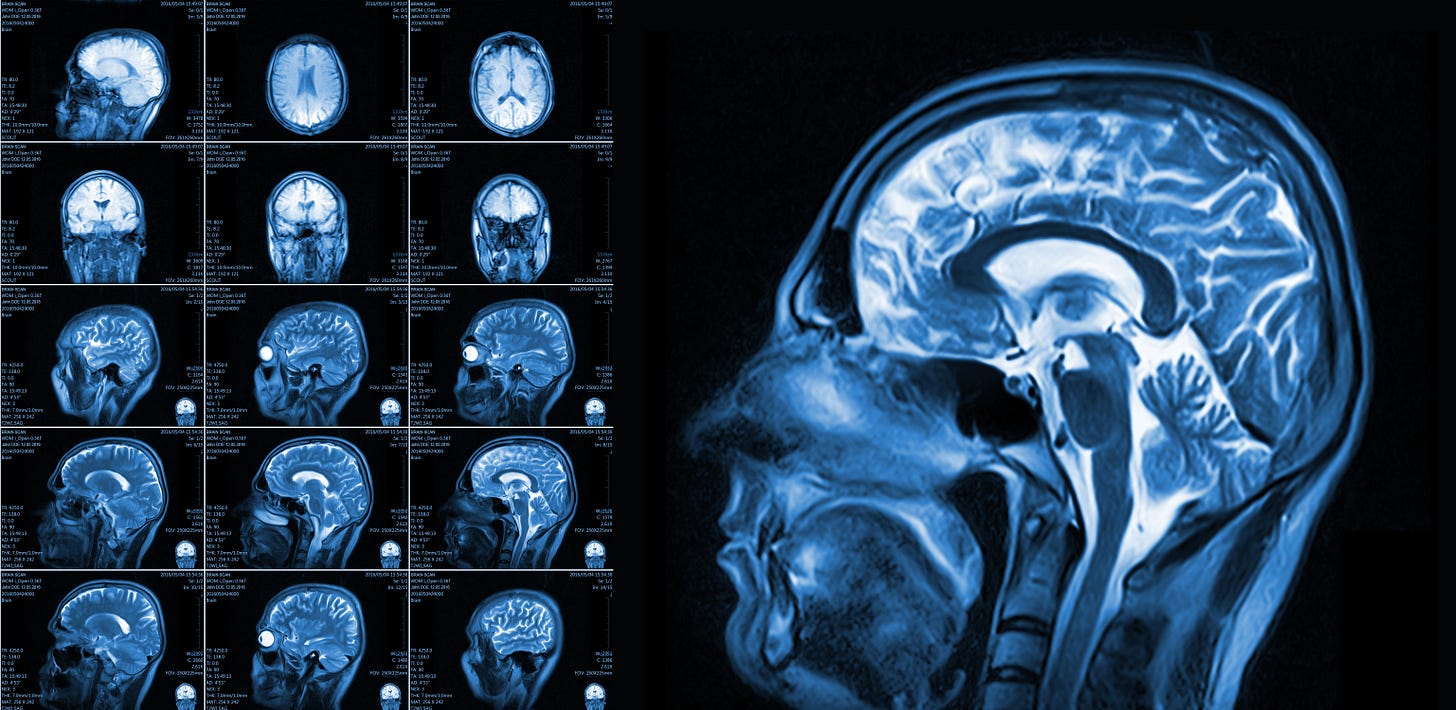

Blood transfusion targets in acute brain injury: Review (Updated)

This review was first published in October 2024; it is updated here with important new results from the SAHARA trial (English et al NEJM 2024), with a series of (rough) meta-analyses of recent data. -Ed.